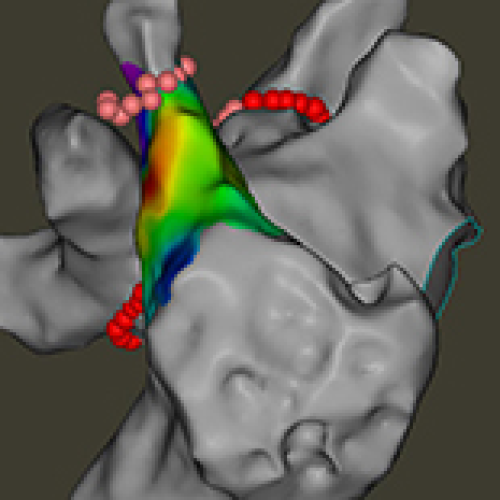

12 May 2024 : Clinical Research

Evaluation of an Optimized Workflow for the Radiofrequency Catheter Ablation of Paroxysmal Atrial Fibrillation

Luqian Cui, Shihua Cui

DOI: 10.12659/MSM.943526

Med Sci Monit 2024; 30:e943526

Luqian Cui, Shihua Cui, Jingchao Li, Haijia Yu, Huihui Song, Yingjie Chu, Shujuan Dong

5,205